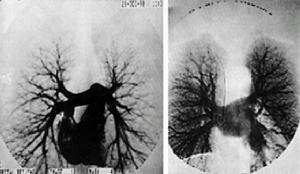

法布里病--影像1967年Brady等闡明了該病的生物化學缺陷。他們認為溶酶體酶醯基鞘氨醇己三糖苷酶活性缺陷導致了神經氨醇分解代謝減低從而導致細胞內神經氨醇半乳糖苷醯基鞘氨醇的沉積。上述細胞內沉積物a末端連線一個半乳糖苷殘基。由於人們對這一特異酶缺陷的認識,現在可以準確地診斷半合子的男性,並可以辨認雜合子女性攜帶者以及在宮內受到影響的胎兒。